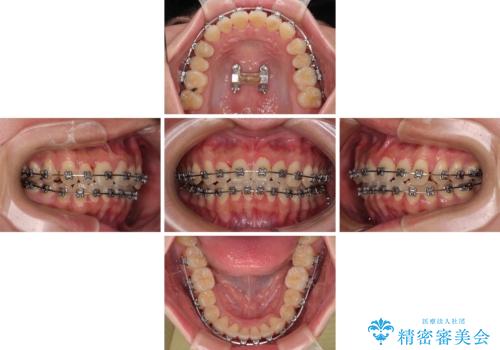

- メタルブラケット

- 1年4ヶ月

- 上下前歯のデコボコやクロスバイトを気にして来院された患者様です。

上顎歯列が下顎の歯列に対して狭小であり、一部下顎の奥歯が上顎よりも外側に位置している状態でした。

上顎の急速拡大装置を使用して上顎骨を側方に拡大することで上顎歯列を拡大し、下顎歯列も拡大できるようにすることで、歯列を整えることとしました。